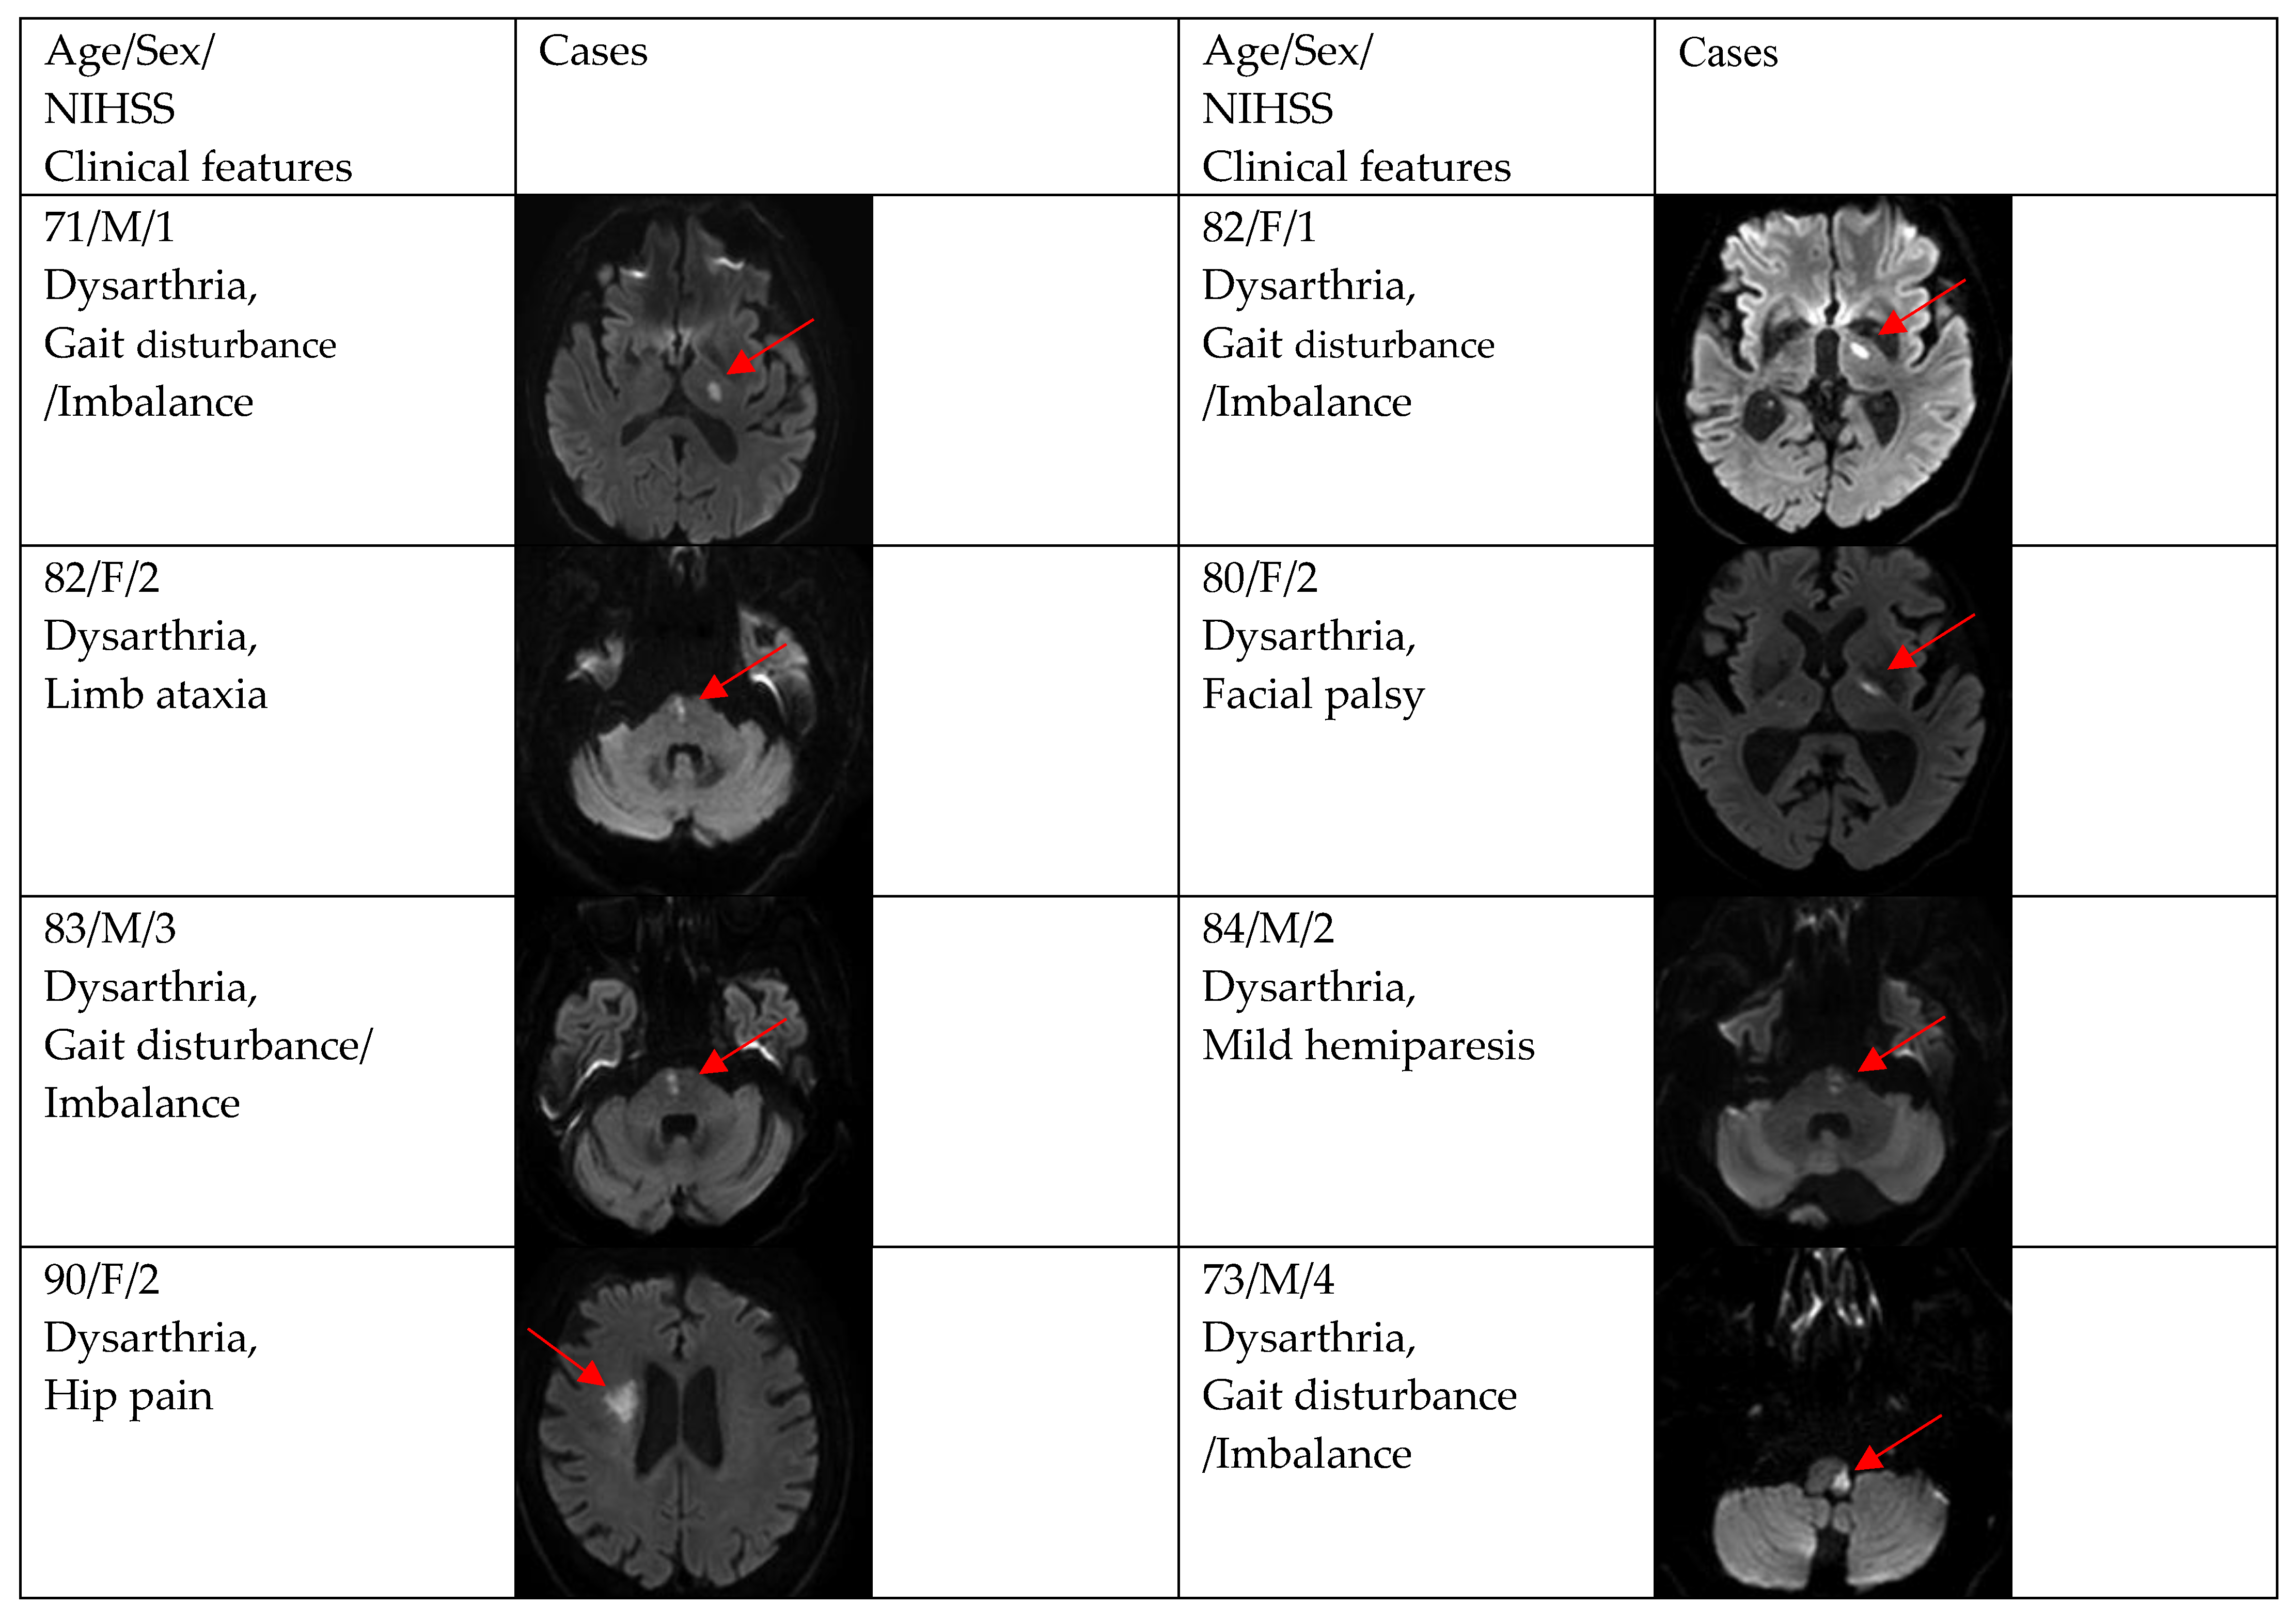

3. Results

| Gait disturbance/imbalance | 9 (19.2) | 1 (7.7) | 8 (23.5) |

| Facial palsy | 8 (17.0) | 1 (7.7) | 7 (20.6) |

| Mild hemiparesis | 5 (10.6) | 2 (15.4) | 3 (8.8) |

| Limb ataxia | 3 (6.4) | 0 (0.0) | 3 (8.8) |

| Diplopia | 1 (2.1) | 0 (0.0) | 1 (2.9) |

| Hip pain | 1 (2.1) | 0 (0.0) | 1 (2.9) |